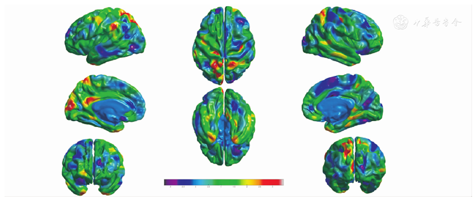

≤60岁和>60岁两个年龄组大脑皮质体积年龄效应不对称性的区域为额上回、额下回岛盖部及三角部、中眶额回、额极、顶下缘角回、缘上回、梭状回、颞极、海马旁回、前扣带回、内嗅皮层(图5),皮质厚度年龄效应不对称性的区域为额上回、额下回岛盖部、中眶额回、楔叶、颞下回、颞极、前扣带回、后扣带回(图6),皮质表面积年龄效应不对称性的区域为额上回、额中回、额下回岛盖部及三角部、中眶额回、额极、顶下缘角回、缘上回、梭状回、颞极、海马旁回、前扣带回、后扣带回、内嗅皮层(图7)。